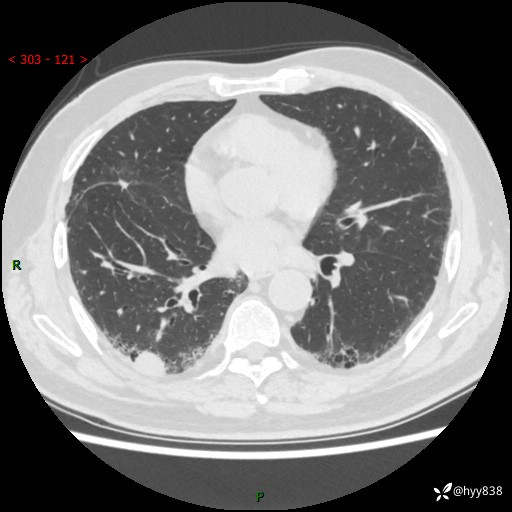

71岁/男,咳嗽伴气促半月。一年前肺手术史,又见两个结节,穿刺结果意外---结果公布~

【现病史】:患者半月前无明显诱因出现咳嗽、咳痰,为白色粘痰,无明显加重与缓解因素,伴气促,无发热,无大量脓痰,无胸痛、咯血,无哮鸣音,到我院就诊,胸部CT示右肺结节增大,并口服药物治疗无明显好转,具体用药不详,为求进一步治疗随来我院,经门诊以“孤立性肺结节”收入我科。 病程中患者精神、饮食可,睡眠不佳,大小便正常,体力下降,体重未见明显下降。

[既往史]:2022-06于当地第一人民医院确诊慢阻肺,现规律使用杰润(1次/日);2023-04-06于当地市第一人民医院行胸腔镜右肺上叶楔形切除术+右肺上叶切除术+淋巴结清扫术+胸膜黏连松解术,确诊为右肺鳞癌 pT2aN0M0 Ib期

【检查】:胸部CT平扫+增强